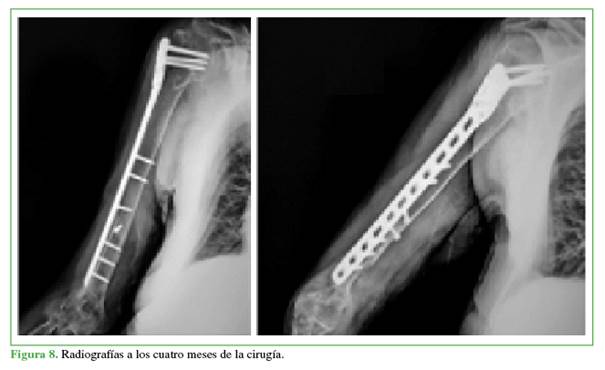

Mujer de 71 años, con fractura bifocal del húmero derecho Maresca tipo A2, 11A2 y 12A1 de la clasificación AO4 (Figura 6); traumatismo con un mes de evolución. Se respetó la táctica quirúrgica antes descrita.

Como dato técnico de valor, se efectuó la reducción y estabilización provisionales del trazo distal con hilos extrarresistentes (Fiberwire®) utilizando el punto de Niza8 para el bloqueo (Figura 7), sintetizando definitivamente el foco con dos tornillos transfracturarios y con la placa extralarga de húmero proximal a modo de puente como en los casos anteriores.

El resultado a los cuatro meses de la operación fue satisfactorio con consolidación de la fractura, sin dolor y un puntaje funcional (provisional) de Constant-Murley de 50 (Figura 8). No fue posible localizar a la paciente en los controles posteriores al quinto mes para una evaluación funcional final.